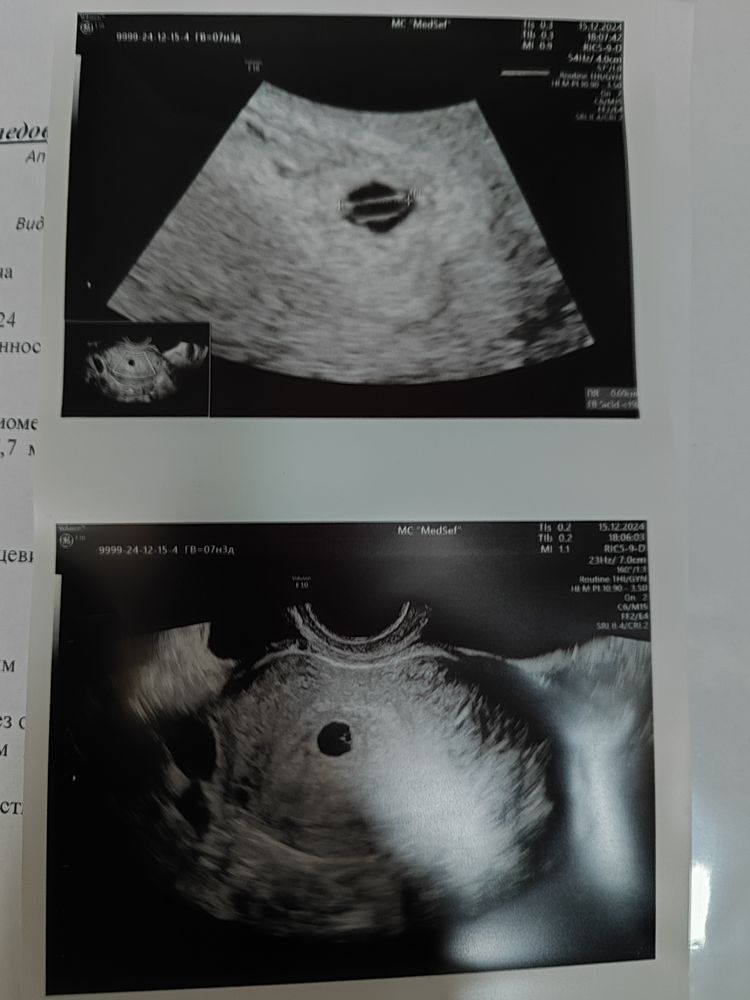

Плодное яйцо за неделю выросло с 4,8 до 7,9 мм. По сроку 7+3, по УЗИ 5+4 (за неделю +2 дня по росту). Желточный мешок неправильной формы, в одной проекции круглое, в другой овальное, сильно вытянуто. Эмбриона нет.